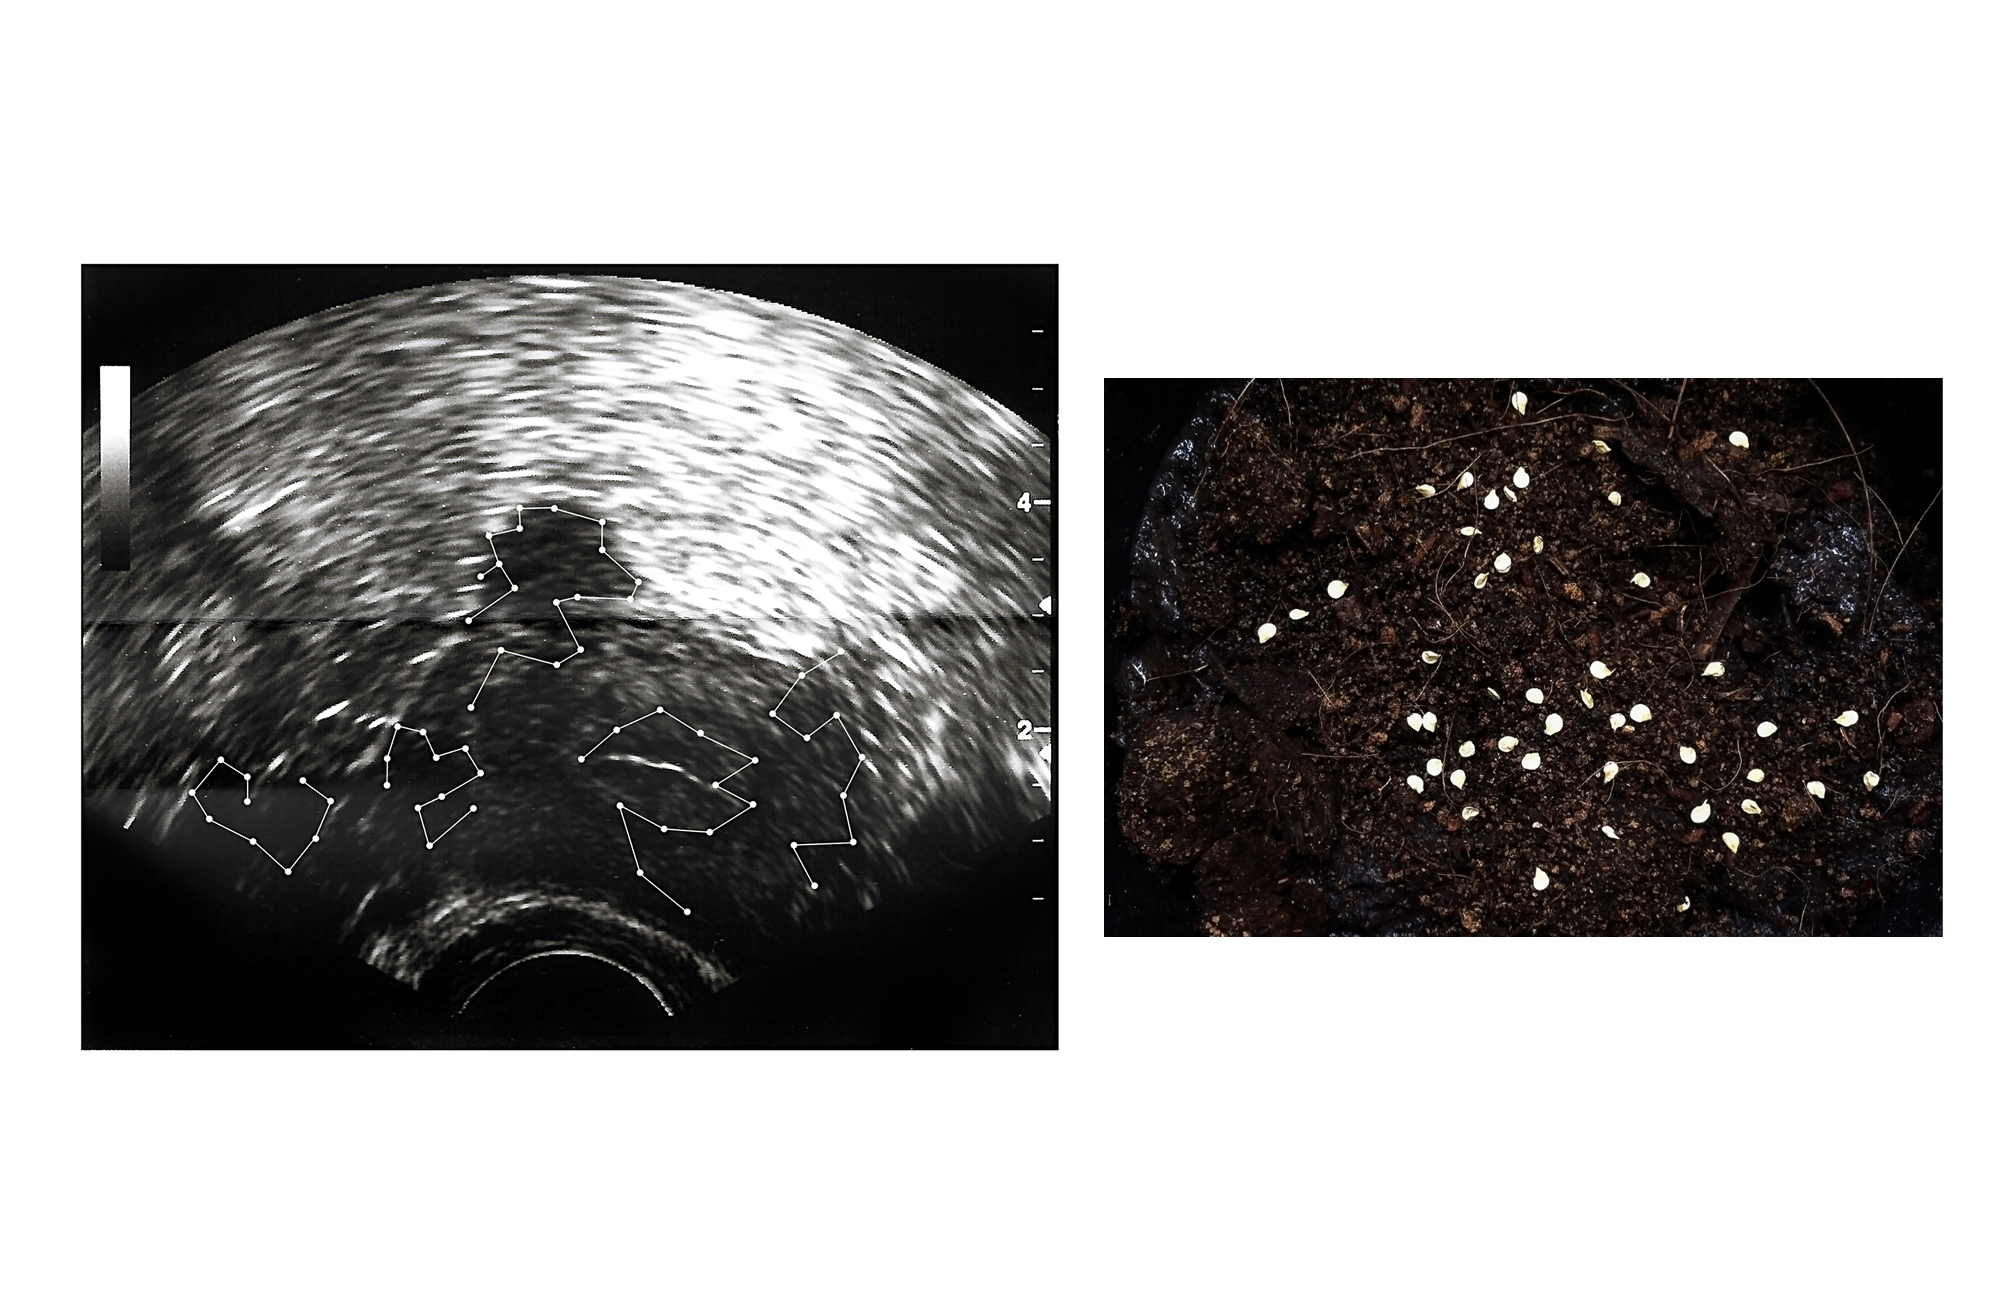

O ensaio transita pelo tema da maternidade. Não Reagente é a falta de escolha, são as surpresas no caminho, aquilo que não nos dá direito de resposta: nem para sim e nem para não. Priscilla não pensava em ter filhos até saber que não poderia tê-los. O impacto do diagnóstico se transformou em necessidade de fotografar. A infertilidade passou a ser um objeto a ser investigado e trabalhado. A pesquisa começou com reação. Entrevistou mulheres. O seu corpo-mãe negativado virou uma questão. “Como você se imagina, se você não tivesse sido mãe?”, perguntou a algumas que o foram. Assustou-se com as respostas. Sentiu o peso do não sobre as suas costas e o peso do sim sobre os ombros de outras. Começou a produzir imagens questionando como as mulheres, vivem, sentem e reproduzem o discurso de uma sociedade patriarcal de que a vida só tem sentido quando se é mãe. Também encarou conversas com quem escolheu não ser. E sentiu o gosto leve – mas nem tanto – que experimentava quando ainda possuía o poder de optar. Não Reagente.

Até que grávida. Até que, obra quase terminada, plot twist. Grávida. Reagente. E ela não sabia reagir. Poder de escolha roubado mais uma vez. Até que mãe – as fotografias, antes não reagentes, precisam encontrar um novo corpo. Nova pesquisa, nova busca. Hormônios reagem. Substâncias que nenhum laboratório fotográfico daria conta, por tanta alquimia. Revelação. Fixação. Ocitocina. Leite. Sangue. Preto, branco e vermelho. Pele e papel. Filho. Sexo. Espelho. Roupas. Comida. Casa. O que ainda não reagiu? O que cabe na maternidade e na não maternidade, no corpo de uma mulher? O que cabe no poder de escolha e na cria? Quem cria quem, afinal? Não Reagente é diálogo e desabafo. É questão urgente. É política daquelas que vêm das entranhas. É imagem e gesto, além de verbo. É respiro e grito. É sobre ser mulher e tudo mais – e tudo menos. É sororidade, acolhida e doação. Não Reagente é processo terapêutico para quem abre a porta para recebê-lo. Priscilla pariu um filho e está parindo uma obra. E não quer deixar a opção de não reagir.